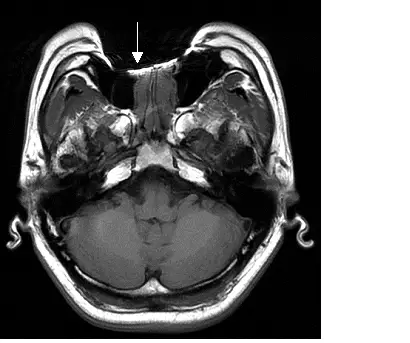

下圖為頭部 MRI 影像,箭號所指假影,最可能是何種原因所造成?

本圖為頭部軸向(axial) MRI 影像,切面位於後顱窩(posterior fossa)/顱底(skull base)水平,可清楚辨識小腦(cerebellum)、腦幹(brainstem)及雙側顳葉(temporal lobes)等結構。白色箭號指向影像前方中線區域(對應口腔/上齒列解剖位置),可見明顯的影像異常,其特徵包括:

- 局灶性訊號喪失(focal signal void):箭號所指處出現完全黑暗的不規則區域,訊號完全缺失

- 幾何變形(geometric distortion):假影周圍的解剖結構出現明顯的空間扭曲,正常組織輪廓失真

- 訊號堆積(signal pile-up):在訊號缺失區域的邊緣可見異常亮帶,為被錯誤定位的訊號堆積所致

- 假影位置固定:假影精確位於口腔/牙齒區域對應的解剖位置,不隨相位編碼方向分布

上述四項特徵構成典型的**磁敏感性假影(susceptibility artifact)**表現,與金屬假牙(如鎳鉻合金 Ni-Cr、鈷鉻合金 Co-Cr)所處位置完全吻合。